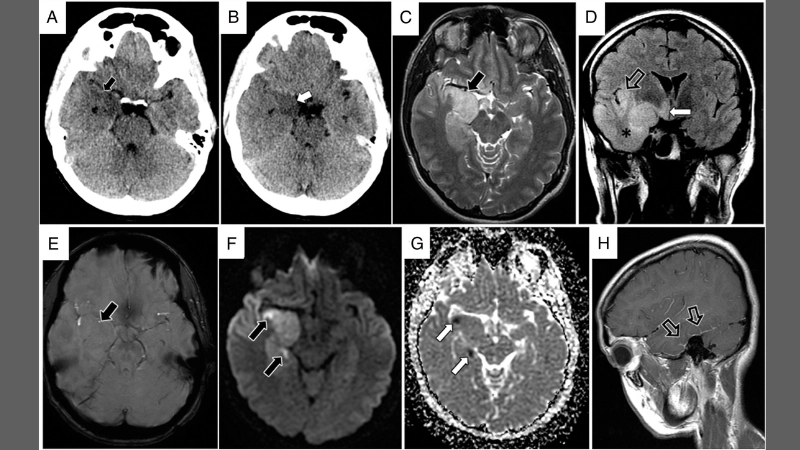

Image description of Herpes Simplex Encephalitis

Herpes Simplex Encephalitis is a rare but serious brain infection caused by herpes simplex virus. It leads to fever, headache, confusion, seizures, and potential long-term neurological damage. Early detection and treatment are crucial for recovery.

Encephalitis diagnosis needs MRI and lab tests